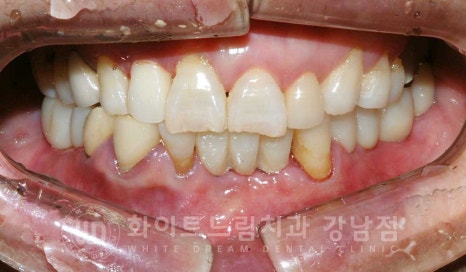

총 치료 기간 : 23.08.18 - 24.01.16

동일 인물이며 동일 환경에서 촬영됨.

초기 잇몸뼈 흡수가 심했던 부분들도 잇몸뼈가 잘 형성되었고

함께 식립한 임플란트도 이상 없이 제 기능을 발휘하고 있습니다.

환자분처럼 수술 시 잇몸뼈가 굉장히 없으셨던 경우는

치료 후 관리를 더욱 열심히 해주셔야 합니다.